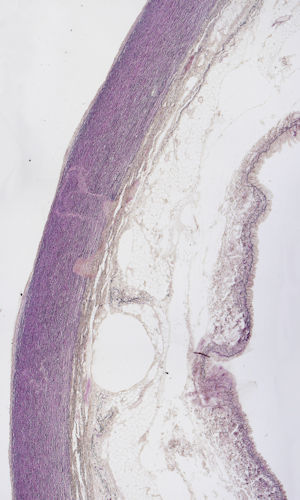

Elastic artery: Cross section through aorta to show elastic fibres (R/F)